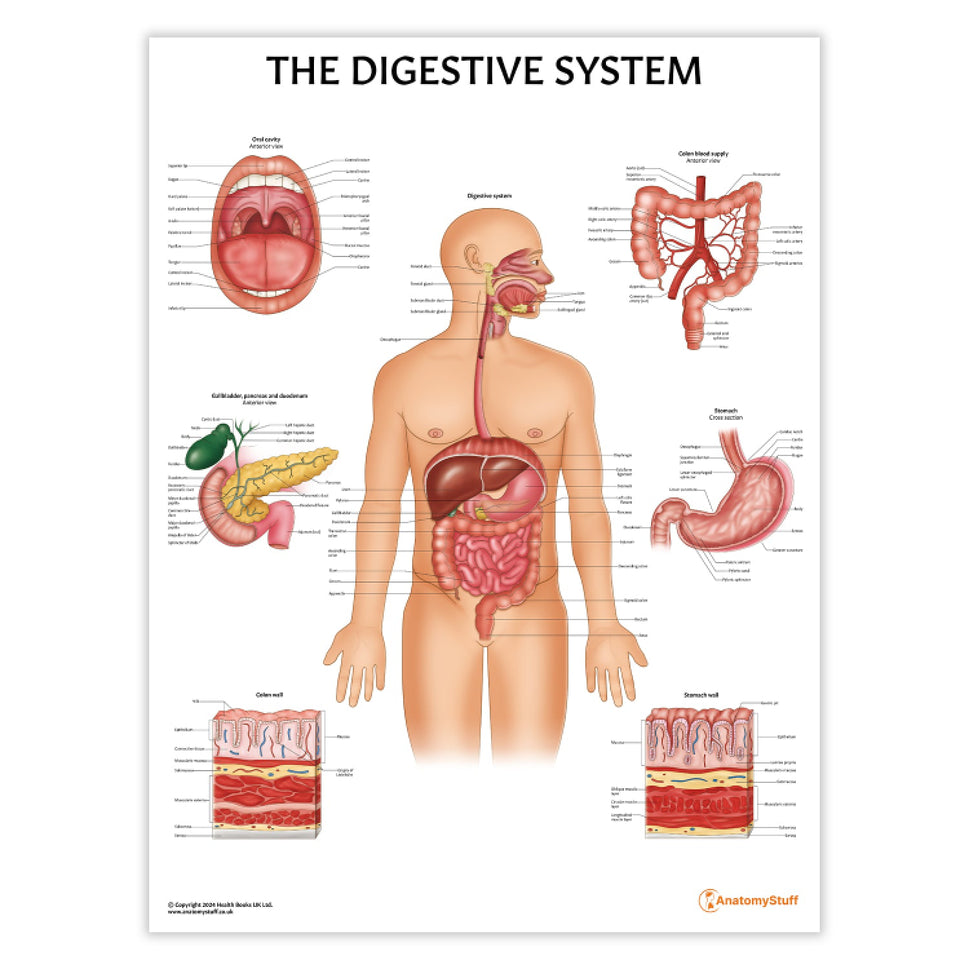

Enhance medical education with our collection of digestive system anatomical models including the stomach, liver, gallbladder, pancreas & colon models. Discover the anatomy of healthy organs as well as common gastrointestinal diseases such as stomach ulcers, gallstones and liver cirrhosis. Our digestive system anatomy posters are ideal for study and patient education.

At AnatomyStuff we stock a diverse range of digestive system anatomical models to suit your training needs. From budget models and affordable medical education posters to highly advanced 3D printed bowel models, you can transform medical training and patient education. As well as our own exclusive collection, we are proud resellers of 3B Scientific, Anatomy Lab, Denoyer-Geppert Science Company, ESP Models, Erler Zimmer and GPI Anatomicals. Explore our exclusive collection of digestive system anatomy charts, posters, fine art prints and digital anatomy study guides. Discover the anatomy of key organs like the liver, stomach, pancreas and bowel as well as the pathophysiology of common conditions like peptic ulcer disease, coeliac disease, IBD and much more. We have anatomy posters suitable for school children all the way up to medical degree level. From a liver anatomy poster to a digital study guide all about common GI disorders, find exactly what you need right here to enhance medical training and patient education.